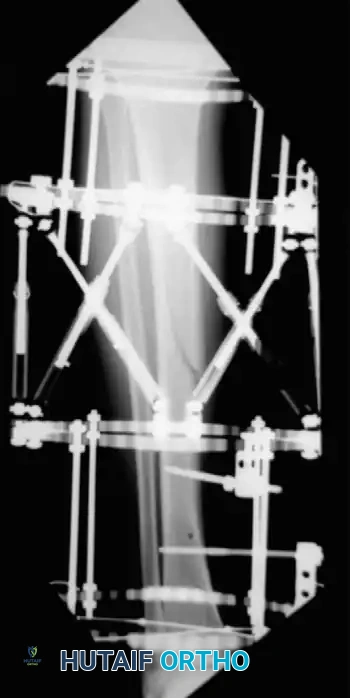

Advanced Surgical Technique: Circular External Fixation

While IM nailing is ideal for diaphyseal fractures, external fixation—particularly circular ring fixators (Ilizarov or Taylor Spatial Frame principles)—is invaluable for severe open fractures, highly comminuted metaphyseal-diaphyseal fractures (AO Type C), and fractures with extensive periarticular involvement.

The following represents a masterclass, step-by-step approach to the application of a circular frame for complex tibial shaft fractures with articular extension.

Step 3: Frame Assembly and "Clamshelling"

Once the reference wires are in place, the frame is assembled around the limb.

- "Clamshell" the distal ring (open the ring, place it around the leg, and close it), positioning the ring directly on the transverse reference wire. This critical step ensures that the knee and ankle joints will remain parallel when the distal and proximal rings are eventually connected.

- Attach the remainder of the wires to the free ring. Because the wires may not lie directly in apposition to the ring due to the contour of the leg, build up to the ring by using various posts and washers of different heights to avoid bending the wires and displacing the fracture.

Step 4: Symmetrical Tensioning

Proper tensioning of the wires is what provides the circular frame with its unique biomechanical stability (beam loading).

- Tension the opposing olive wires symmetrically using two-wire tensioners.

- Crucial Step: Perform this tensioning strictly under fluoroscopic control. Asymmetrical tensioning can cause unequal compression across fracture lines, leading to iatrogenic displacement or varus/valgus malalignment.

Step 5: Proximal Extension and Shaft Alignment

Once the periarticular block is secured, attention turns to the diaphyseal comminution.

- Attach the distal ring block to the proximal rings using threaded rods equipped with conical washers. These washers allow for multi-planar variability in reducing and maintaining the overall mechanical axis.

- Use the ring at the level of the proximal shaft extension to reduce proximal shaft comminution.

- Use additional olive or smooth wires to manipulate and maintain shaft alignment, effectively "pulling" large butterfly fragments into the construct. Attach these wires to the mid-distal ring and tension them under fluoroscopy so the reduction can be observed in real-time.

Associated Surgical & Radiographic Imaging